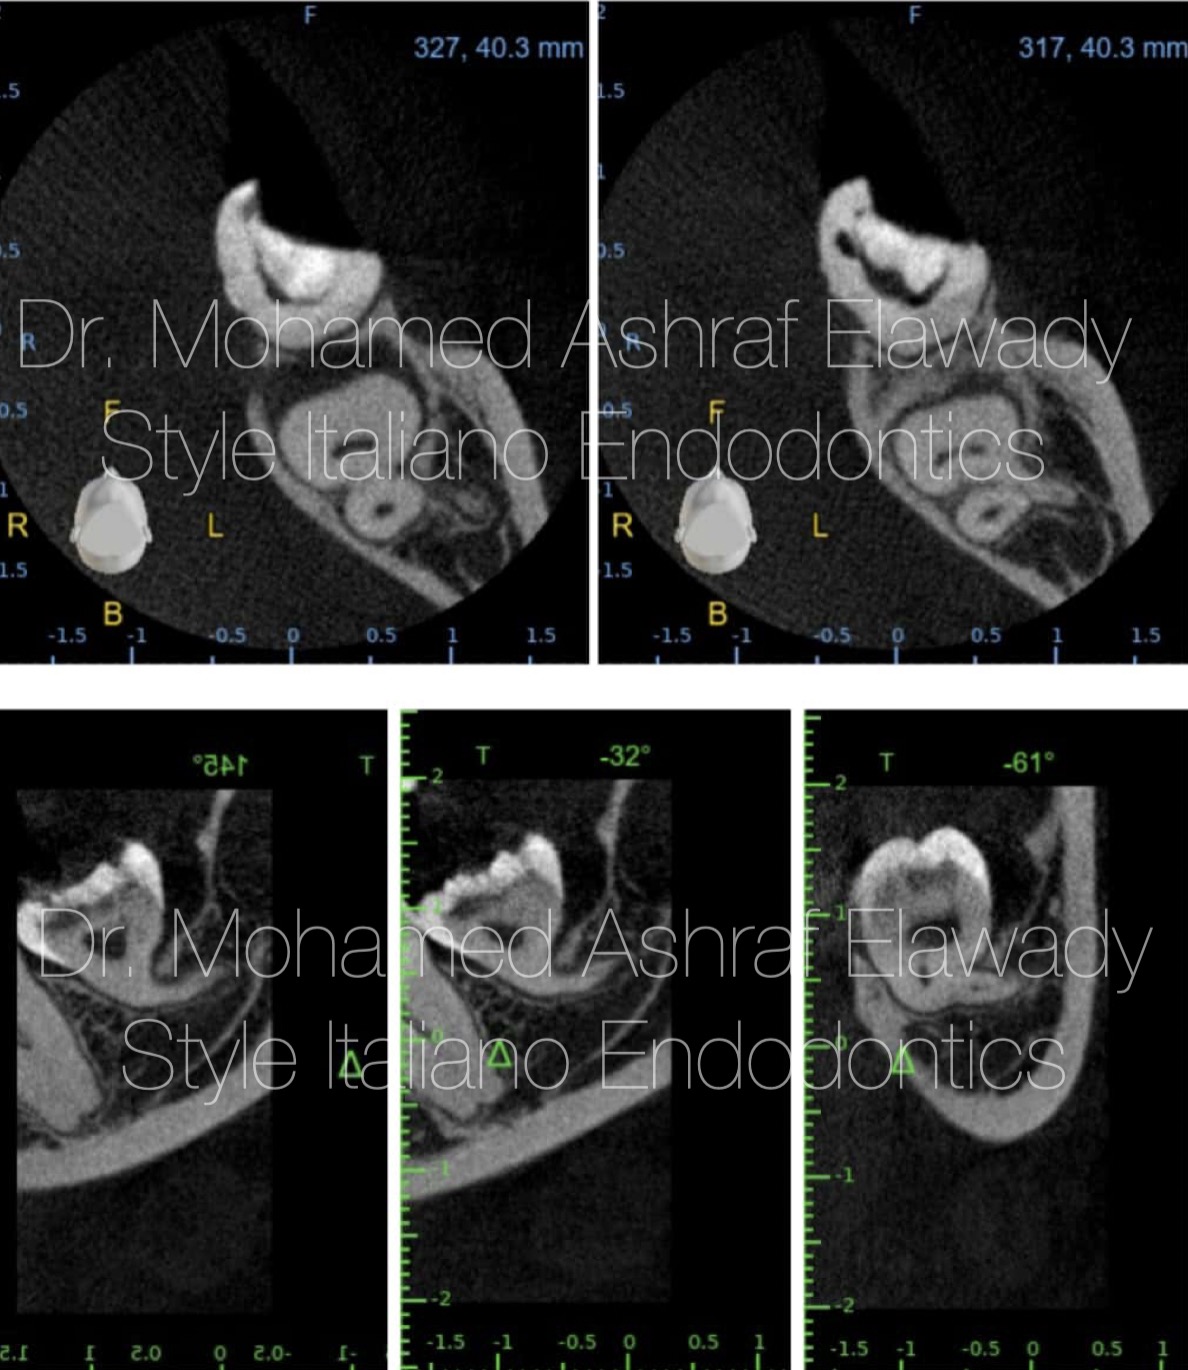

In difficult cases CBCT plays a crucial role in assessing the complexity and anatomy of severely curved canals, providing detailed 3D imaging that aids in accurate treatment planning and improving navigational precision during instrumentation.

Fig. 2